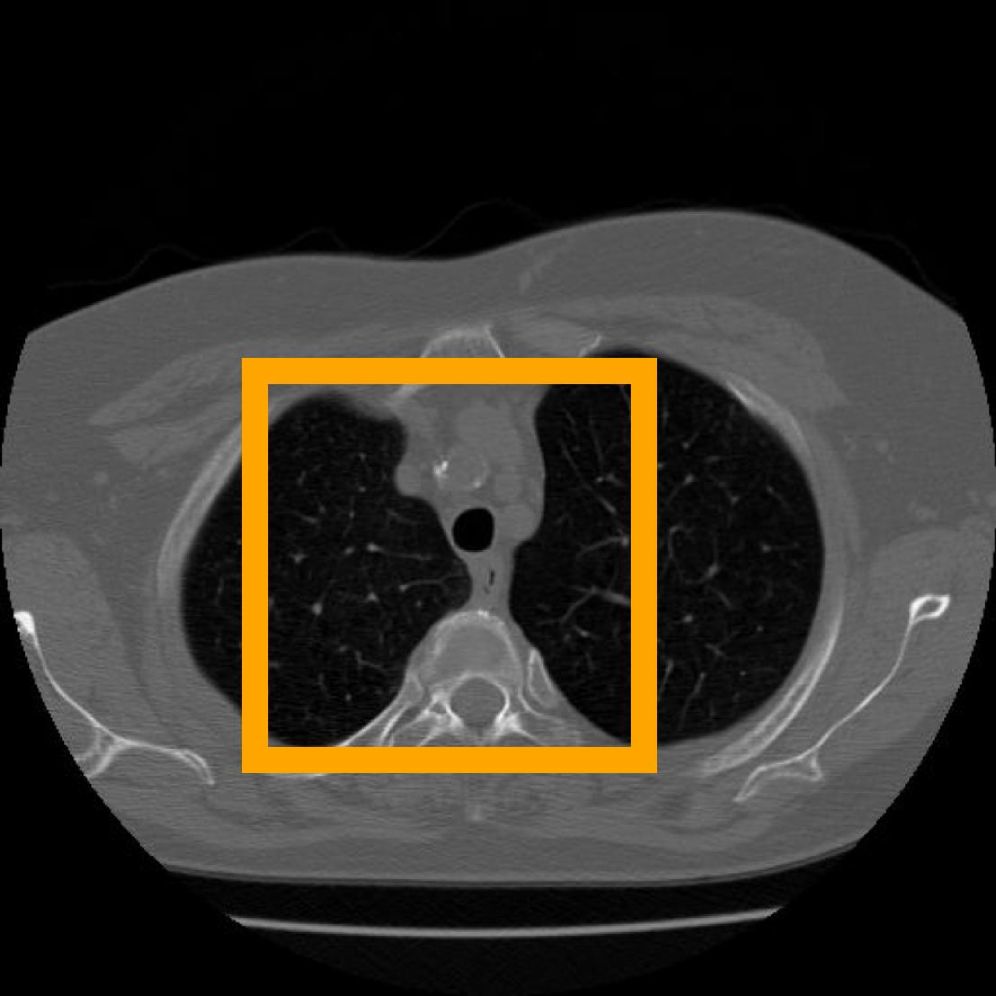

Figure 10: The visual comparison of different compression methods on a CT Heart Segmentation image.

Figure 11: Zoomed-in view of the highlighted region in Figure 10.

Figure 12: The visual comparison of different compression methods on another CT Heart Segmentation image.

IV-B3 Visual Comparison

Figures 7 and 8 present representative examples from the CIL dataset and their zoomed-in regions, respectively. For the CT Heart Segmentation dataset, Figures 10 and 12 illustrate typical reconstruction results, while Figures 11 and 13 further enlarge local regions to compare structural details. Across both datasets, COLI preserves fine structures and global continuity well even at relatively low bpp. Specifically, on the CIL dataset, COLI attains the lowest bitrate among INR-based methods while still maintaining clear texture details. On the CT Heart dataset, COLI also operates at a low bpp within the INR family and delivers superior visual quality with improved detail fidelity and smoother structural presentation. The zoomed-in regions show fewer blocking artifacts and smoother transitions, making COLI especially suitable for large images and medical images. These visual results validate that INR-based compression can achieve efficient storage with reliable perceptual consistency, offering practical advantages for real-world large-scale image processing.